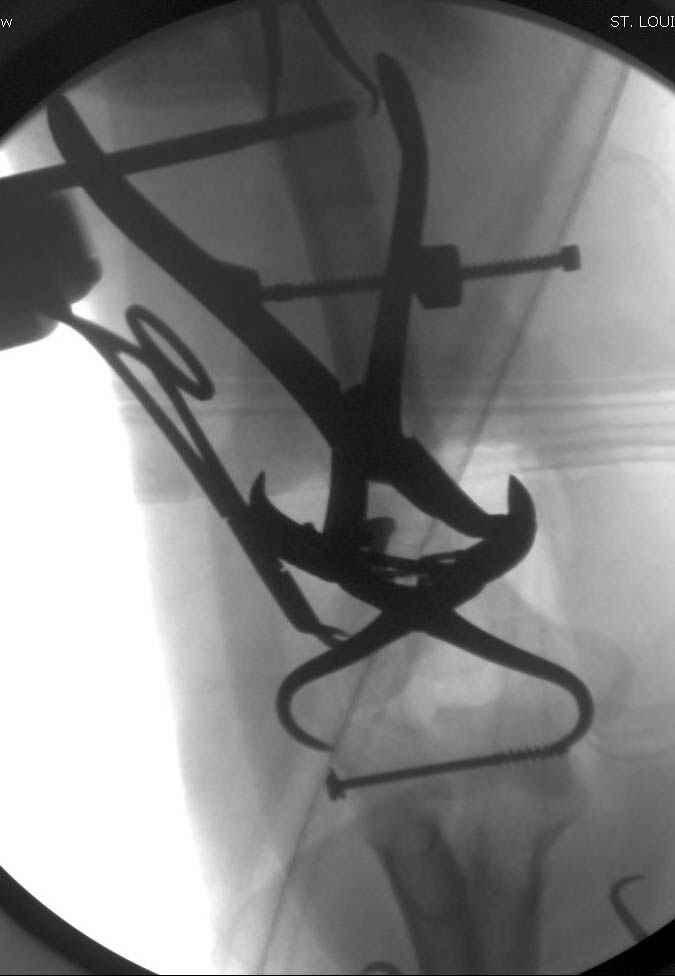

Djoldas Kuldjanov, M.D. 09 Сентябрь 2005, 20:07

Примерный случай, только перелом был открытый, в задне-медиальной стороне рана около 2 см по характеру "изнутри кнаружи", неврологический статус со слабостью сгибания мизинца, также слабая абдукция и аддукция указательного пальца и сгибания в кисти.

Больному сделали обработку и наложили временный аппарат внешной фиксации плечо-предплечье.

На шестой день сделали открытую репозицию чрезлоктевым доступом двумя locking plate, локтевой нерв был ушибленным, после операции положительная динамика в Flexor Carpi Ulnaris. Фиксацию локтевого отростка произвели tension band technique с дополнительным шурупом.

Этапы операции на снимках....